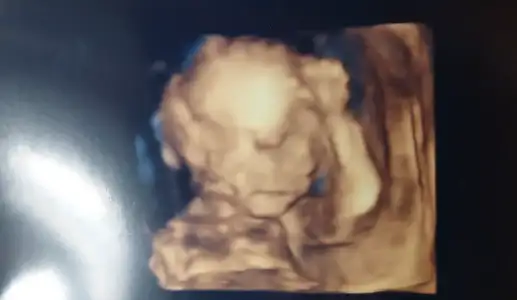

Bu da kızımın son pozu 🎀 daha ilk bakar bakmaz kız bebek dedi doktorumuz 😂 ilk bacak arasını gösterdi hemen sağolsun 🥰